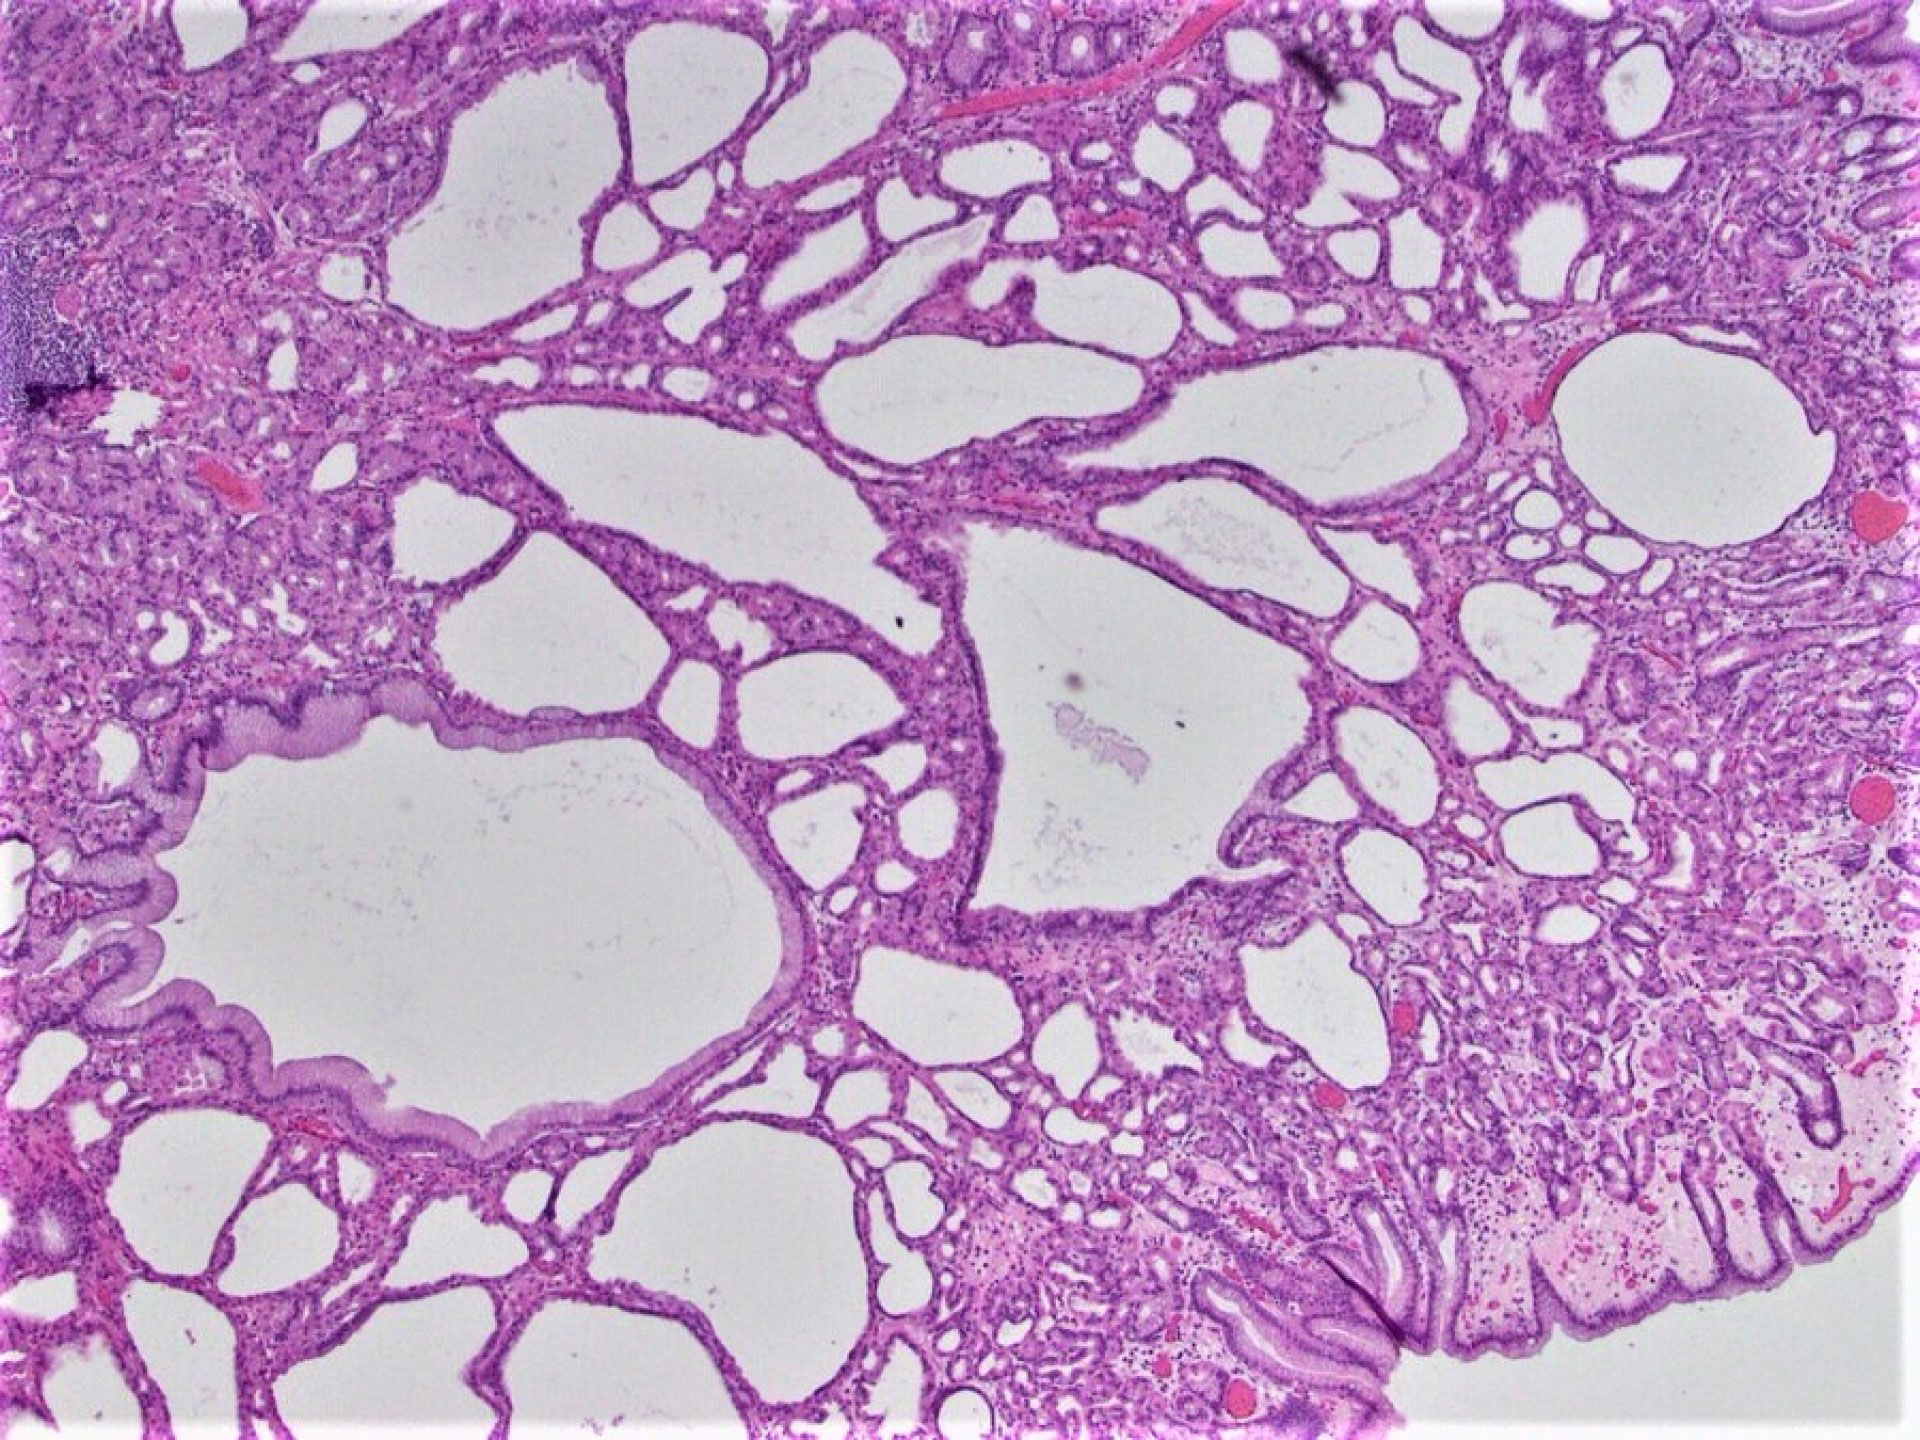

The latest endoscopic examination revealed a gastric fundic gland polyp (Figure 1) as well as numerous colonic polyps (Figures 2-4). The colonic polyps included inflammatory polyps and tubular adenomas. High-grade dysplasia was not identified in any of the polyps.